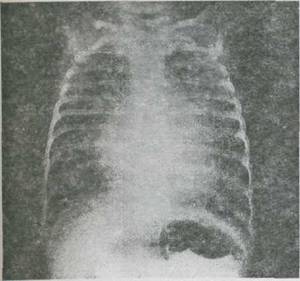

Fig. 9-2, Defect septal ventricular nerestrictiv cu hipertensiune pulmonara. Radiografie cardiopulmcnara; cardiomegalie importanta

bombarea trunchiului arterei pulmonare, congestie vasculara pulmonara

Radiografia cardio-pulmonara demonstreaza cardiomegalia legata de cresterea dimensiunilor ambilor ventriculi si a atriului stāng, dar silueta cardiaca ramāne nesugestiva pentru acest diagnostic. Hipervascularizatia pulmonara este evidenta si frecvent se remarca tulburari de ventilatie, variabile, "mobile", generate de compresiunea vasculara a cailor aeriene si puseelor de suprainfectie bronho-pulmonara divers intricate.